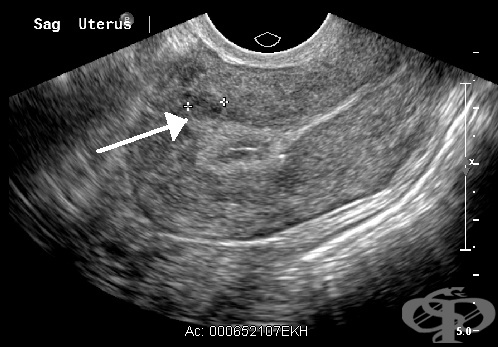

Лейомиомата се диагностицира чрез тазов преглед и ултразвуково изследване.

Основно значение за поставянето на диагнозата миома имат клиничната картина и образните изследвания, предимно ехографията.

Поставянето на диагнозата миома обикновено не е трудно, но понякога могат да съществуват и затруднения. Основно значение се отдава на огледа и палпацията, образните изследвания, параклинични изследвания, сондирането на матката и други. Посредством тези методи може нерядко да се определи размерът, б...

Миома Матка с миоми Видове миома Симптоми при миома Гинекологичен преглед Ехография на миома Хистероскопия Хистерография Хирургично лечение на миома Аблация на ендометриума